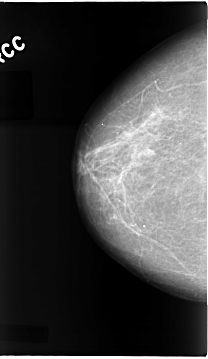

C_0072_1.LEFT_CC

LEFT_CC LINES 4704 PIXELS_PER_LINE 2632 BITS_PER_PIXEL 12 RESOLUTION 50 NON_OVERLAY